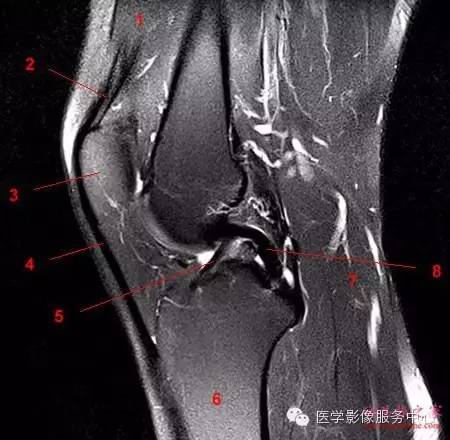

以内侧副韧带损伤(MCL)为例,可分为Ⅲ级

Ⅲ级:MCL 完全断裂。Ⅲ级损伤,因韧带完全撕裂,使其连续性中断,并伴有韧带的增粗肿胀,整条韧带结构与肌肉信号混合,界限消失,不能辨认其结构走形,在T2WI 或STIR 上呈弥漫性高信号,有时韧带断端呈波浪状改变,关节囊内可见不等量的积液影像